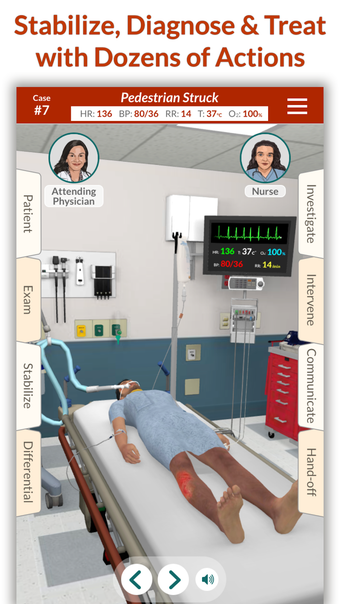

Full Code - Emergency Medicine Simulation è un'applicazione Android sviluppata da Minerva Medical Simulation Inc. È una versione completa con licenza di un'applicazione di stile di vita che rientra nella sottocategoria medica. È un'applicazione di simulazione intuitiva, mobile-first che offre oltre 160 casi virtuali realistici e un'interfaccia coinvolgente simile a un gioco, preferita dai professionisti medici di tutto il mondo. L'applicazione è progettata per aiutare gli studenti e i professionisti medici a acquisire fiducia nel trattamento di casi complessi e offre 0,5 crediti AMA PRA Categoria 1™ per ogni caso Full Code giocato con Full Code Pro+CME.

L'applicazione consente agli utenti di esercitarsi in diagnosi cliniche rare e rischiose in un ambiente sicuro in modo da poter affrontare casi complessi del mondo reale con fiducia. Con oltre 160 casi in 31 specialità, Full Code consente di esercitarsi in simulazioni mediche on-demand ogni volta che si ha una pausa, ovunque ci si trovi. L'applicazione è ottimizzata per la portabilità e l'accessibilità ed è disponibile su qualsiasi dispositivo mobile, desktop o tablet. Full Code è accreditato attraverso l'ACCME e, con la sua sottoscrizione PRO+CME, gli utenti possono completare i loro requisiti di formazione medica continua (CME) con sfide di simulazione flessibili e piacevoli. È un'applicazione eccellente per i professionisti medici che vogliono migliorare le proprie competenze e acquisire fiducia nel gestire casi complessi.